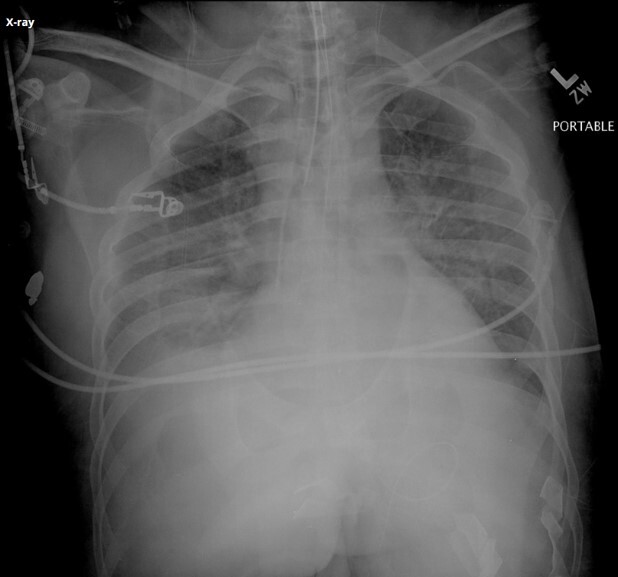

What artifact is seen superimposed over the scapula and lateral chest wall in the attached image?

A

Patient artifact (bra straps)